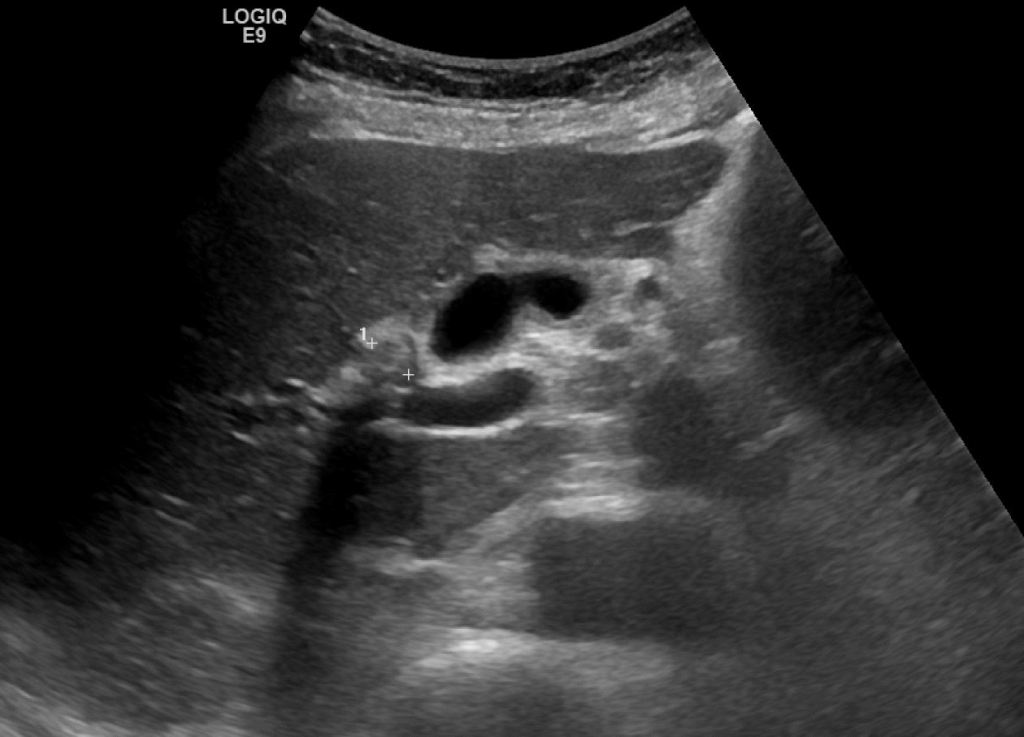

CT에서 보이던 우측 간내담관결석이 보이며, 담관의 확장이 같이 확인됩니다.